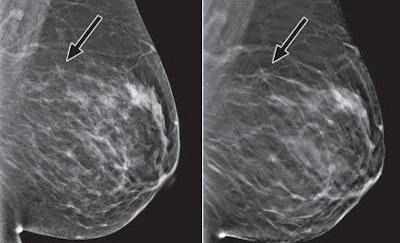

Digital breast tomosynthesis (DBT) when used as a screening tool for breast cancer reduces recall rates by 37% and increases the detection of invasive cancers by 54%, according to a new study published online May 22 in the American Journal of Roentgenology.

Rose and colleagues used procedure outcome-related databases to evaluate recall, biopsy, and cancer detection rates, and they calculated PPVs in the clinical breast imaging practice before and after the introduction of tomosynthesis for routine screening mammography. In all, 13,856 women received 2D screening mammography studies without the use of tomosynthesis, while 9,499 women underwent both 2D and 3D mammography. Images were interpreted by six radiologists, and their performance with the two protocols was analyzed (AJR, May 22, 2013).